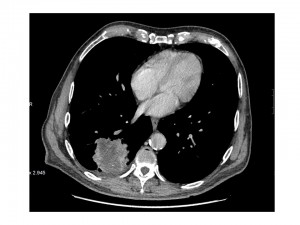

Justificación: Debemos realizar un TC para observar la lesión con mayor precisión. El TC nos permite delimitar con claridad la morfología de la lesión y confirmar qué estructuras están afectadas y la extensión a distancia.Como vemos se trata de una masa y será necesario realizar una BAG eco-guiada, pero para ello previamente habremos evaluado el TC.

¿Qué observas en las siguientes imágenes?